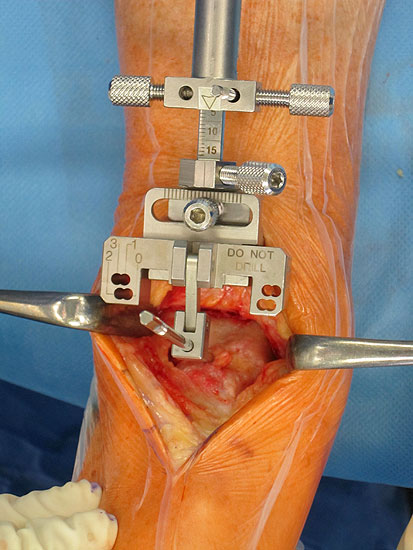

• Prothesenplanung anhand von Röntgenschablonen (Abb. 1 und 2).

• Instrumentarium SALTO II/Talaris

• Stichsäge (Schutz des Innenknöchels, mediale Ausrichtung der Tibiakomponente)